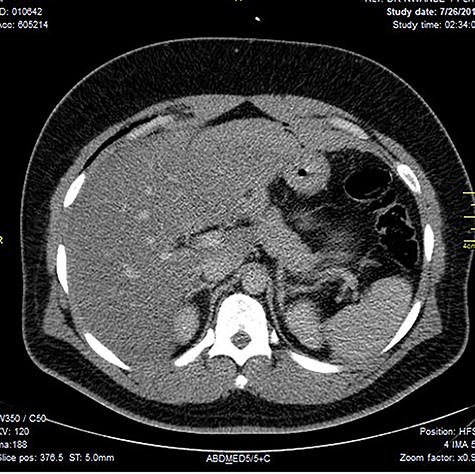

Chest X-ray was normal as shown in Fig. 1. Focused abdominal sonography for trauma (FAST) scan showed mild left perihepatic collection necessitating a thoracoabdominal computerized tomography (CT)-scan which showed external oblique muscle laceration with intermuscular air lucencies and grade 2 hepatic injury as shown in Figs 2–4. Other blood work-up were normal. No other injury was found on secondary survey. His wound was explored under local anaesthesia, primarily repaired, and he was discharged after 24 h of close observation.

Showing lucent air densities tracking through the right intercostal muscles and abutting on the liver in the epigastrum with associated subcapsular haematoma in the left lobe of the liver.